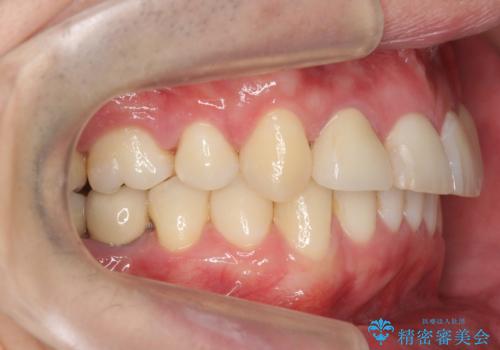

八重歯の矯正+歯のないところにインプラント

- 八重歯を主訴に来院。

下の歯がないところに、奥歯が倒れこんでいたため、矯正治療で倒れこんだ歯を起こして、インプラントを植立しました。

上の前歯が下の前歯に大きく重なっており、過蓋咬合を呈していました。

上顎の小臼歯2本、下顎の親知らずを抜歯しています。

八重歯の移動のため、矯正用ミニスクリューを使用しています。